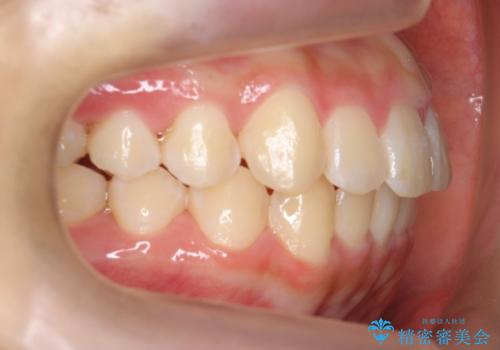

中学生のマウスピース矯正 歯を抜かずにキレイに

- 10代女子

- 矯正装置

- インビザライン フル

- 治療期間

- 1年11ヶ月

- 出っ歯を主訴に来院。

(1)インビザラインで歯を少し削って並べる。歯は抜かない。・・・歯を抜かなくて良い。歯磨きが楽、装置も目立たない。通院は3ヶ月に1回。

非抜歯ながらも、矯正用のインプラントを使用し、出来るだけ前歯を下げるように工夫して治療しました。

治療結果にはお母様、ご本人も含め、大変喜んでいただきました。

歯を抜かずに治療しましたが、治療前後で口元が悪化しないように治療することができました。